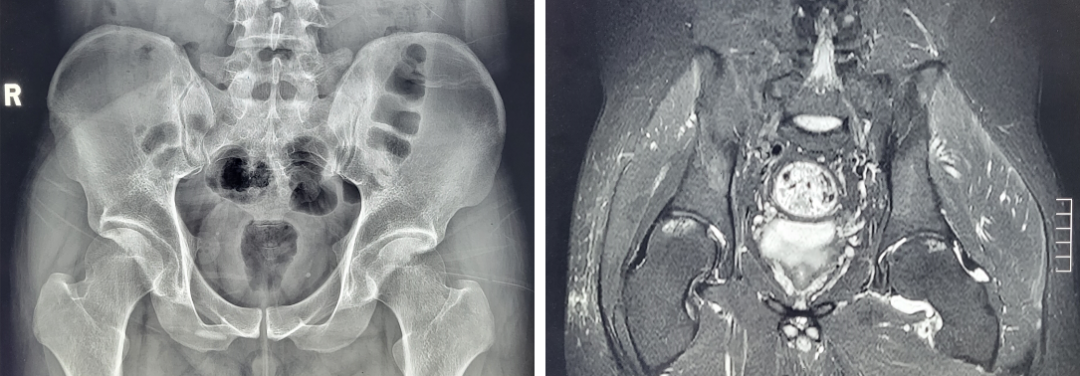

近日,患者小陈因酒后突发左侧髋部剧痛、不能活动,急诊入我院骨科“入院时简直生不如死,关节不敢伸直,甚至不敢做任何活动,特别影响睡觉和休息”,小陈痛苦回忆到。经检查,我院骨科诊断为“左侧髋关节痛风性关节炎急性发作”。主管医生丁虹表示:患者为青年男性,既往有高尿酸血症病史,未规范治疗和严格控制饮食,结合患者症状体征及检查结果,痛风性关节炎诊断明确,但像小陈这样重的症状,并不多见。明确诊断后,对患者进行了正规保守治疗,尿酸值降至正常,疼痛症状好转,但活动恢复仍不理想,骨科曹治东主任考虑与关节通风结晶及炎症因子沉积有关,决定予以髋关节镜下探查、清理、关节囊切开减压术,术后患者疼痛症状进一步缓解,左侧髋关节活动完全恢复。“终于可以睡个安稳觉啦!”小陈一脸惊喜。

术前影像检查